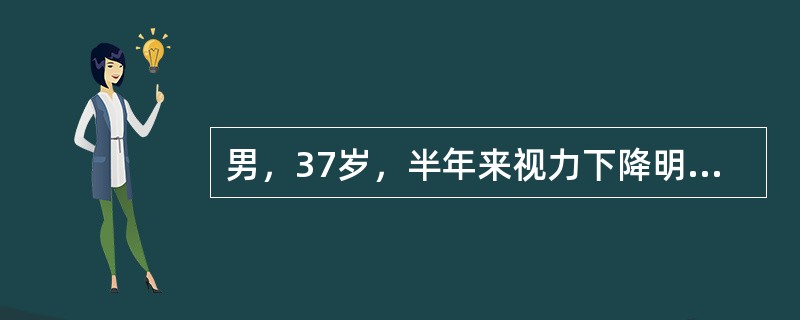

男,37岁,半年来视力下降明显,近1个月失明,CT如图,最可能的诊断是

A.色素膜黑色素瘤伴视网膜脱离

B.色素膜血管瘤伴视网膜脱离

C.色素膜转移瘤伴视网膜脱离

D.色素膜神经瘤伴视网膜脱离

E.黑色素细胞瘤伴视网膜脱离

[单选题]男,37岁,半年来视力下降明显,近1个月失明,CT如图,最可能的诊断是A.色素膜黑色素瘤伴视网膜脱离B.色素膜血管瘤伴视网膜脱离C.色素膜转移瘤伴视网

[单选题]男,37岁,半年来视力下降明显,近1个月失明,CT如图,最可能的诊断是A.色素膜黑色素瘤伴视网膜脱离B.色素膜血管瘤伴视网膜脱离C.色素膜转移瘤伴视网膜脱离D.色素膜神经瘤伴视网膜脱离E.黑色素细胞瘤伴视网膜脱离